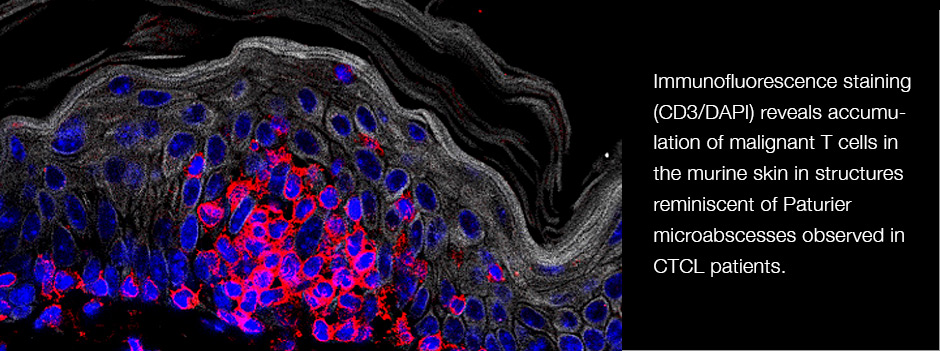

We are leveraging of our expertise in conditional gene targeting, cutting edge multimodal single-cell sequencing, and our great relationship with clinical collaborators to pursue projects related to both basic immunology (B and T cell development) and clinically relevant questions in infection, autoimmunity and cancer.